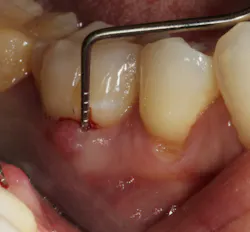

In other words, even experienced clinicians who access a root surface with flap surgery are sometimes limited in the amount of detoxification that can occur due to the depth of the defect and conventional instrumentation. (11) Further limitations with mechanical access to defects can come in the form of furcations with multirooted teeth. The diameter of the entrance to root furcation is usually smaller than the average tip of a curette, which can make access difficult (figures 1 and 1a). Molars with bone loss that includes furcations are often downgraded in prognosis due to this access difficulty. (12)

Figure 1: Molar with periodontal abscess due to furcation involvement

Figure 1a: Deep Class II furcation with an entrance smaller than the diameter of a curette tip